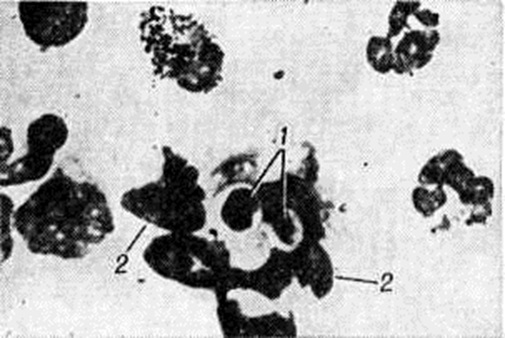

КандидозКандидоз (candidosis; синонимы: кандидамикоз, поверхностный бластомикоз, соормикоз, candidiasis, moniliasis, oidiomycosis) — инфекционное заболевание кожи, слизистых оболочек и внутренних органов, вызываемое дрожжеподобными грибками (грибы рода Candida). Заболевание впервые описано Б. Лангенбеком в 1839 год, хотя оно было известно со времён Гиппократа под названием stomata aphtoides и aphta infantis (Кандидоз Гален). В 1848 год Берг (F. Th. Berg) впервые установил наличие дрожжеподобных грибков в тканях больного человека. Беркхаут (М. Berkhaut) в 1923 год среди дрожжеподобных грибков выделила род Candida. Термин Candida был принят в 1939 год III Международным конгрессом микробиологов. Кандидоз встречается во всех странах мира, особенно часто в поясе тропического и субтропического климата. Число больных различными клинический, формами Кандидоз, особенно висцеральными, имеет некоторую тенденцию к росту. ЭтиологияВозбудителем Кандидоз наиболее часто является Candida albicans, реже С. tropicalis, С. krusei, С. pseudotropicalis, С. stellatoidea и некоторые другие виды. Род Candida (класс Fungi imperfecti) включает св. 80 видов, характеризующихся круглыми, овоидными, реже цилиндрическими, а иногда неправильной формы клетками. Молодые клетки — в диаметре от 2 до 5 микрометров, зрелые — несколько больше. Истинного мицелия дрожжеподобные грибки не имеют; они образуют цепочки (псевдомицелий) из удлинённых клеток, которые соприкасаются друг с другом узким основанием (так называемый перетяжки), длина псевдомицелия до 12—16 микрометров Клетки размножаются прорастанием и многополюсным почкованием (2—3 и более дочерних почек). С. albicans и С. stellatoidea образуют на концах псевдомицелия споры с плотной, обычно двойной клеточной стенкой — хламидоспоры (рисунок 1). Кандида — аэробы; они часто являются сапрофитами слизистых оболочек рта, кишечника, влагалища, кожи. Встречаются в почве, на фруктах и овощах. Для питания они используют из азотистых веществ белки, пептоны и аминокислоты. Кандида считаются условно патогенными микроорганизмами; их патогенность для человека и животных в значительной степени зависит от состояния макроорганизма (смотри полный свод знаний ниже). Наиболее распространенными для выращивания кандида (оптимальная температура 30—37°) являются жидкая среда Сабуро, пивное сусло, мясопептонный глюкозный агар. Для выявления хламидоспор наиболее пригодны среда Чапека — Докса с добавлением твина-80, картофельный агар с желчью, кукурузный и рисовый агар. Кандида сохраняют свою жизнеспособность в культурах (в высушенном состоянии) в течение нескольких лет, переносят многократное замораживание и оттаивание в воде и почве. Они выдерживают конкуренцию со многими микроорганизмами по длительности существования на различных продуктах, например, в кислом молоке, квашеной капусте, фруктовых соках и другие. В культурах и патологический материале грибки погибают при кипячении в течение нескольких минут. Губительное действие оказывают 2—5% растворы фенола и формалина, хлорамина, лизола, йодиды, бораты, сульфат меди и цинка, перманганат калия и другие химический вещества; фунгицидно действуют растворы анилиновых красителей (генцианвиолет, малахитовый зелёный, метиленовый синий и другие). ЭпидемиологияХорошая приспособляемость многих видов рода Candida к окружающей среде обеспечивает им широкое распространение, а также носительство человеком и животными. Например, С. albicans может быть обнаружен на коже, слизистых оболочках и в испражнениях почти у 20% здоровых людей. Кандидоз болеют телята, ягнята, жеребята, домашняя птица и другие; отмечены заболевания и диких животных. Некоторые представители рода Candida ассоциируют с нормальной микрофлорой кожи человека (прежде всего С. albicans). Как источник инфекции наибольшее значение представляют больные свежими формами поражения кожи и слизистых оболочек. |

Рис. 1. | ||